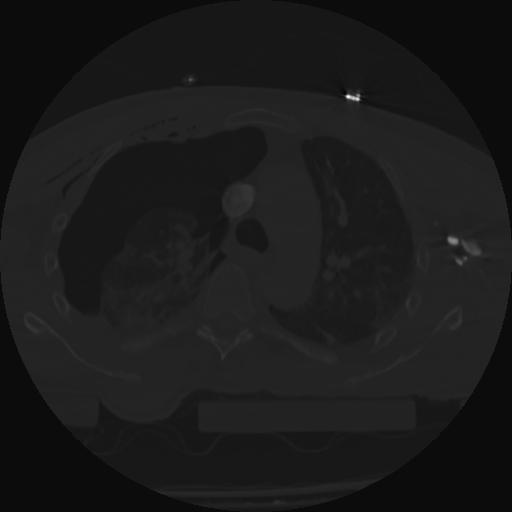

22 ANGIO,CE,Vol,0.5,ANGIO,,